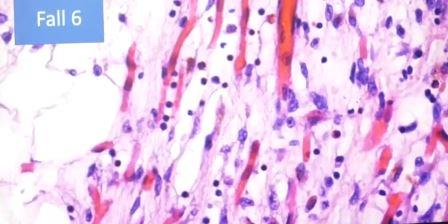

Con aumento se ve la vasodilatación, linfocitos, fibroblastos

Ampliación, linfocitos y granulocitos. Los linfocitos no deben estar allí, pero están omnipresentes, se trata de una epicarditis

Epicardio con infiltración de linfocitos